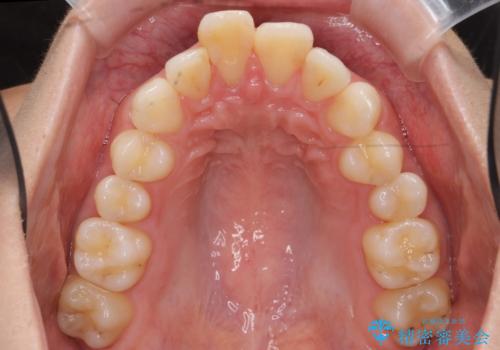

出っ歯 下の歯のガタガタ 下の前歯のみ1本抜歯 マウスピースで1年

下の前歯のがたつきがひどく、非抜歯では難しい状態でした。

古典的な方法では4本抜歯した後、ワイヤー矯正という方法も選択肢には上がりましたが、下の前歯を1本だけ抜くことにし、マウスピースで短期間で治療を終わらせるようにしました。

治療も比較的短期間で終わり、大変喜んでいただきました。

下の前歯を1本抜くと上下の正中はあいませんが、ほとんど目立ちません。